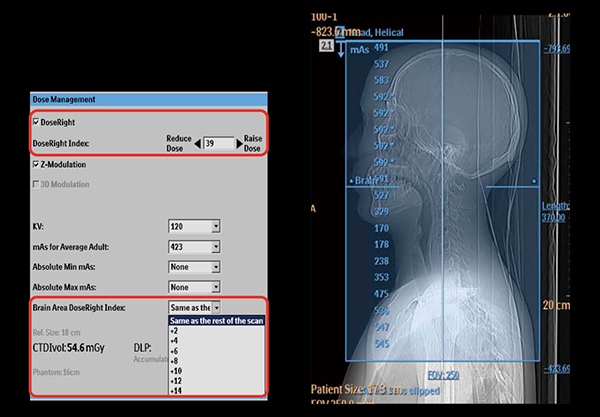

頭頸部領域においても,交通外傷などの救急CT撮影などにて複数部位にまたがった撮影を施行する場合がある。フィリップスでは,CT-AECの線量レベル決定方式としてDose Right Index3)と呼ばれる方式を採用しているが,2013年に頭頸部領域における1回撮影において,CT-AECの画像ノイズレベルを各部位に合わせて設定できる可変型画像ノイズレベル設定技術“Brain Area Dose Right Index”を搭載した。これにより,1スキャンの頭頸部撮影において,頭部のDose Right Indexと頸部のDose Right Indexをそれぞれ指定することが可能である。また,Brain Area Dose Right Indexの指定範囲は,位置決め撮影画像より解剖学的位置を認識し,自動的に設定される(図3)。このBrain Area Dose Right Indexにより,1スキャンの頭頸部撮影における一方の部位が線量過多となる,またはノイズ過多となることを防止することができるため,部位ごとに撮影を行い,画像ノイズレベルの適正化を図ることが不要となり,救急撮影時の検査時間延長やOver RangingによるDLPの増加を懸念する必要がなくなる。

図3 Brain Area Dose Right Index